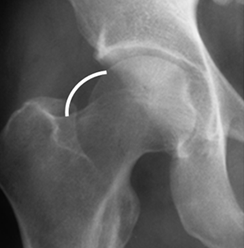

Fig 100. Pinzamiento tipo cam.

Rx AP de cadera. Producido por alteración morfológica del cuello femoral.